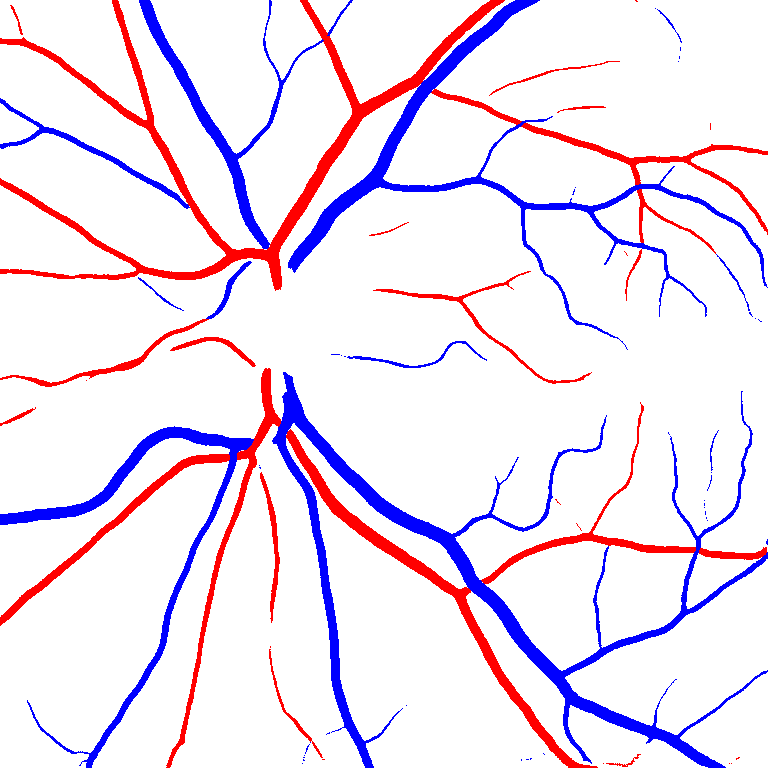

Table VI presents a quantitative comparison of the measured diameters using the segmentation outputs of SegRAVIR and competing approaches. Using the pixel-wise annotated masks, the reference average diameter of the arteries and veins in the test set of the RAVIR dataset were measured as and , respectively. According to our analysis, SegRAVIR can accurately measure the diameter of the vessels and it achieves the smallest MAPE among the competing approaches. Specifically, in comparison to CE-Net, Iter-Net, and DU-Net, respectively, SegRAVIR is on average , and more accurate in terms of MAPE for the measured diameter of arteries and , and in terms of MAPE for the measured diameter of veins. Fig. 6 presents qualitative comparisons of reference and SegRAVIR estimated diameter maps.

(a) (b) (c)

(a) (b) (c)